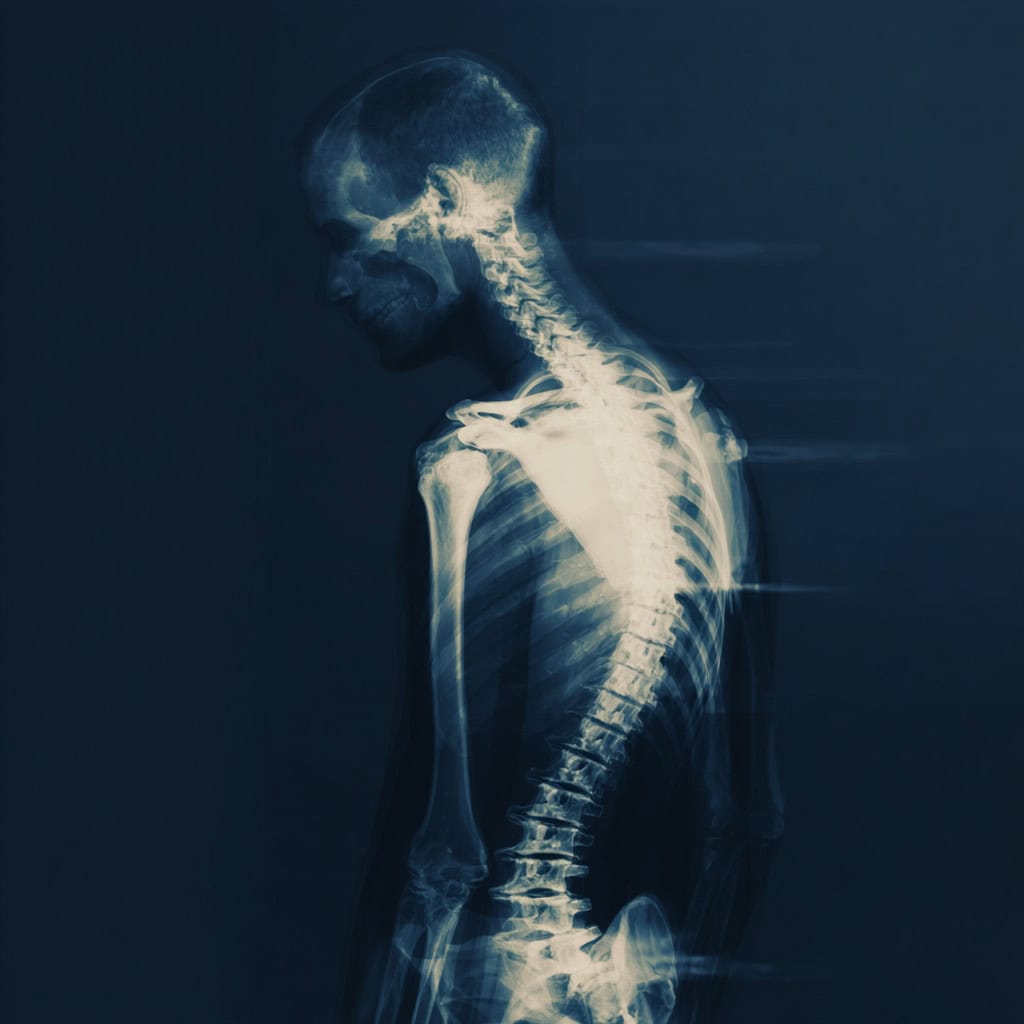

Spine anatomy showing disc and facet joint areas treated with regenerative back pain treatment